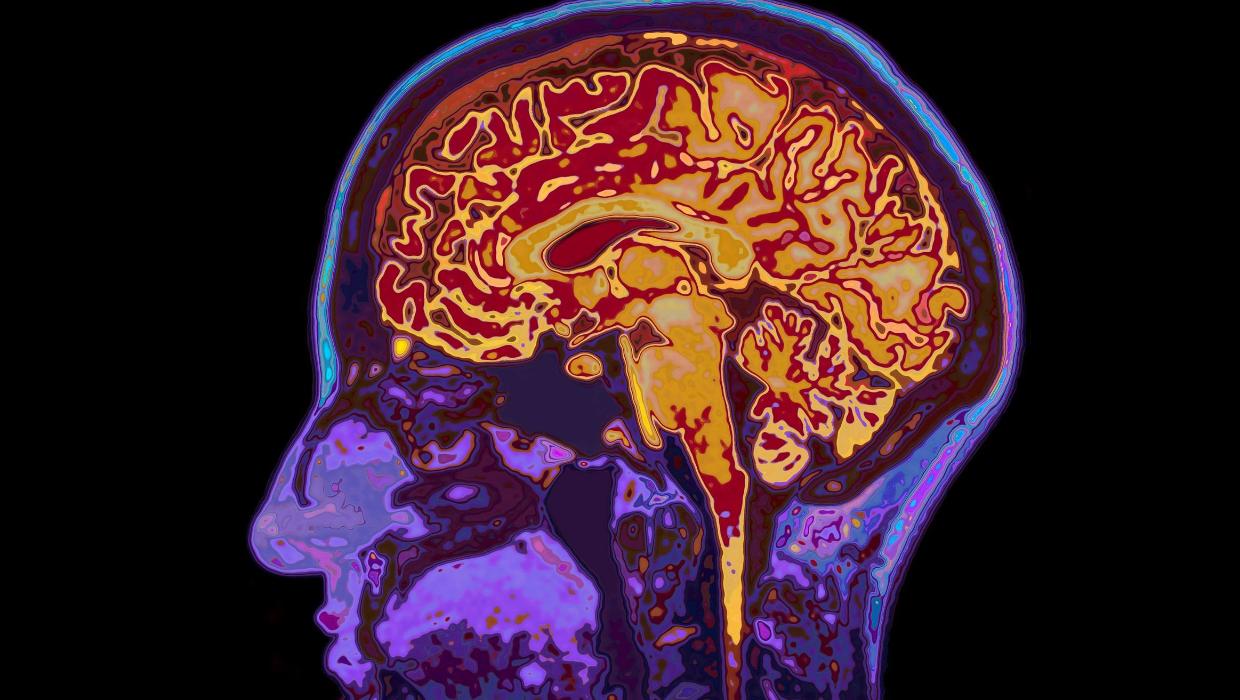

A recent study by the University of Cambridge has uncovered significant insights into human brain development. The research identifies that the brain remains in a state of adolescence until the age of 32, while the aging process begins around 66 years. This study emphasizes five major epochs of brain development, highlighting four critical turning points in an individual’s life.

Understanding brain development has long fascinated scientists, and this research sheds light on the complex timeline of maturation. The study categorizes brain development into distinct phases, indicating that the brain undergoes substantial changes well into early adulthood. According to the findings, these epochs are crucial for cognitive, emotional, and social growth.

The researchers used advanced neuroimaging techniques to map the brain’s developmental trajectories. They discovered that significant changes occur during childhood, adolescence, and early adulthood. For instance, the brain’s ability to process information and regulate emotions continues to develop into a person’s thirties, which challenges traditional notions of maturity.

In contrast, the research also indicates that the formal onset of aging begins at around 66 years. This period marks a decline in certain cognitive functions, although the study notes that individuals can still experience significant growth and learning well into their later years. The findings suggest that the brain is capable of adaptation and change throughout life, emphasizing the importance of continued learning and mental stimulation.

In conclusion, the latest findings from the University of Cambridge highlight that brain development is a lifelong process. Recognizing that adolescence extends to age 32 and that aging starts at 66 opens up new avenues for understanding human potential across the lifespan. This research not only enriches the field of neuroscience but also invites society to rethink how we define maturity and aging.